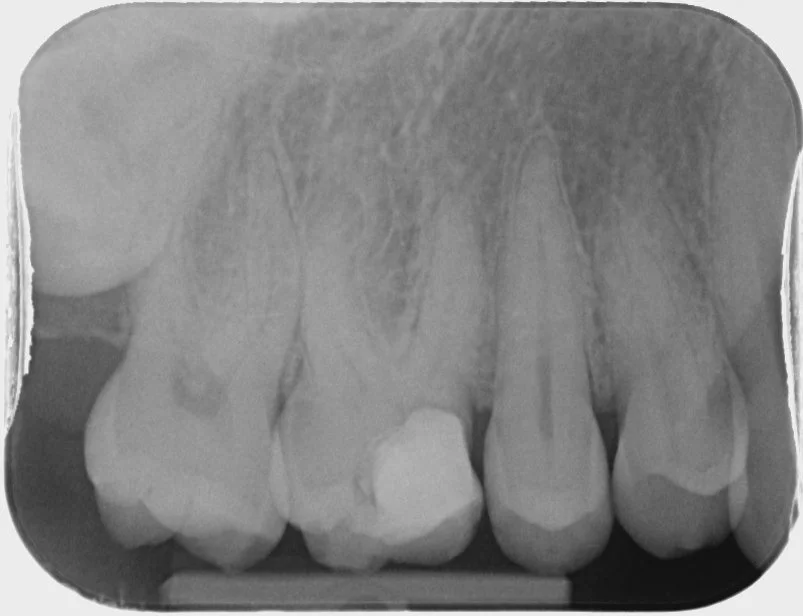

Preoperative film shows failing 16M restoration. Patient presented with irreversible pulpitis on 16.

Through the access cavity, MB1, DB and P canals are readily identifiable. However, the MB2 orifice is hidden underneath a dentine ledge along the mesial wall of the access cavity.